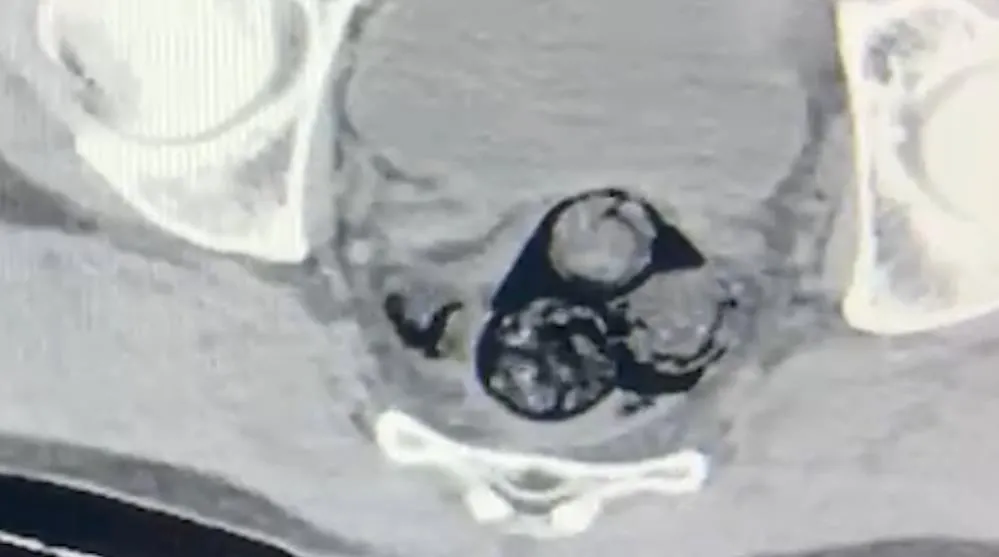

Iğdır İl Emniyet Müdürlüğü Narkotik Suçlarla Mücadele Şube Müdürlüğü ekipleri, yurt dışından Türkiye’ye giriş yapan ve şüpheli hareketler sergileyen A.İ. isimli kişiyi takibe aldı. Yapılan detaylı aramalar neticesinde, şahsın vücut boşluklarında uyuşturucu madde taşıdığı belirlendi. Radyolojik görüntüleme sonucu, şüphelinin makat bölgesinde dört farklı yabancı cisim olduğu ortaya çıktı. Sağlık kontrolünden geçirilerek, çıkarılan cisimlerin içinde toplamda 140 gram metamfetamin olduğu tespit edildi. Uyuşturucu madde taşımak ve ticaretini yapmak suçundan hakkında işlem başlatılan A.İ., Iğdır Adliyesi’ne sevk edildi. Mahkemeye çıkarılan şahıs, tutuklanarak cezaevine gönderildi.